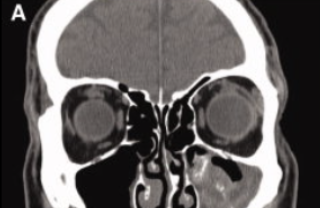

Material hiperdenso em seio maxilar, com calcificações lineares de permeio